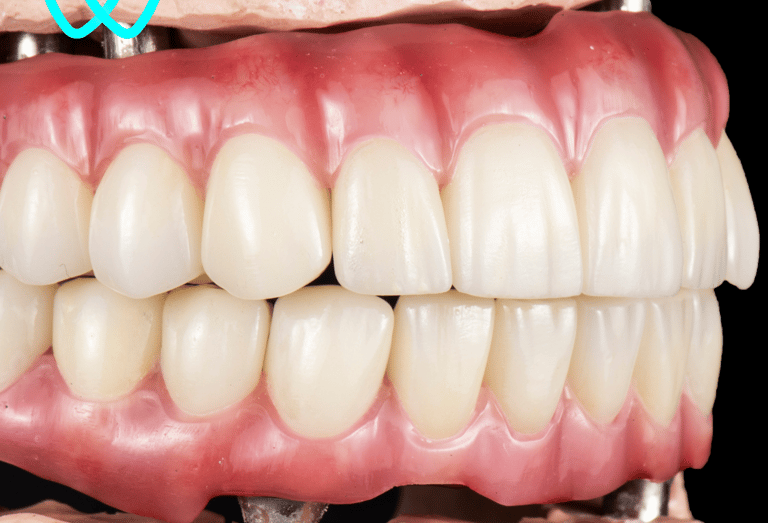

Diseñamos prótesis completas que sustituyen todos los dientes perdidos, mejorando la estética y funcionalidad de tu boca, o prótesis parciales removibles para pacientes que han perdido varios dientes. Nuestras prótesis son personalizadas para garantizar comodidad y un ajuste ideal.

Prótesis dental

Sobredentadura

Las sobredentaduras son una excelente opción para pacientes con pérdida total de dientes. Estas prótesis se fijan sobre implantes dentales, ofreciendo mayor estabilidad, comodidad y confianza al hablar y comer. Incluso ahora podemos realizarlas con implantes subperiósticos para pacientes que antes no se podían rehabilitar.